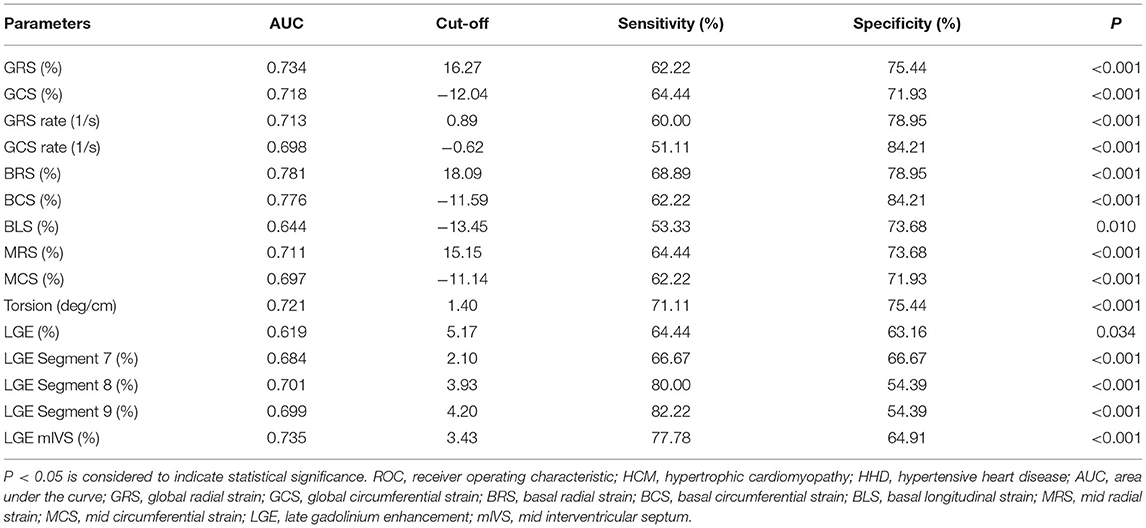

The results of the ROC analysis to discriminate between HCM and HHD are shown in Table 4. GRS (AUC: 0.734, sensitivity: 62.22%, specificity: 75.44%, P < 0.001), GCS (AUC: 0.718, sensitivity: 64.44%, specificity: 71.93%, P < 0.001), and corresponding strain rate could distinguish HCM from HHD. For segmental strain parameters, the AUCs of BRS, BCS, BLS, MRS, and MCS for discriminating between HCM and HHD were 0.781, 0.776, 0.644, 0.711, and 0.697, respectively (all P < 0.001). The torsion cutoff value of > 1.40 differentiated HCM from HHD with a sensitivity of 71.11% and a specificity of 75.44%. The AUC of LGE (mIVS) was 0.735, which was the highest in the global and other segmental LGE analyses (all P < 0.05). Overall, BRS showed the highest diagnostic performance and the value of the AUC was 0.781 (all P < 0.05). On the multivariate regression analysis, the combination model of LGE (mIVS) with GRS obtained the highest AUC value, which was 0.835 with 88.89% sensitivity and 70.18% specificity, respectively (Table 5). DeLong's test showed that the AUC of a combined model of GRS with LGE (mIVS) was higher than those of GRS, GCS, torsion, and LGE (mIVS) (all P < 0.05) (Figure 4).